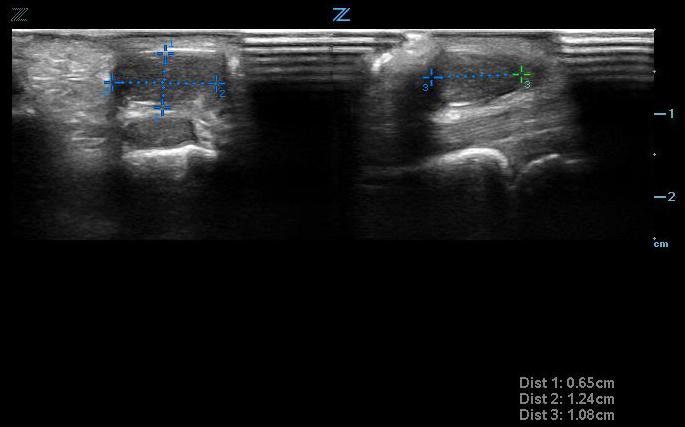

- Ultrasound can help differentiate solid from cystic masses. Ganglion cysts are a common cystic mass that arises from tendon sheaths and joints (Fig. 7). They are filled with a gelatinous material. On ultrasound, they appear anechoic and can cause posterior acoustic enhancement.18 It might be possible to trace the cyst to its origin from the tendon sheath or joint space.

- Figure 4. Small ganglion cyst seen transversely (left) and longitudinally (right) above tendon